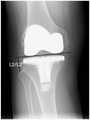

FIG. 2 is a schematic diagram of a knee joint line using the deep learning-based pre-revision surgery planning method for total knee replacement provided in the present invention;

1. the change of the joint line before and after the revision is measured by taking the fibula as a reference point.

As shown in FIG. 2, on the X-ray orthostatic plate of the knee joint, 1 perpendicular line is drawn from the highest point of the fibula to the farthest end (i.e. the lowest point) of the medial condyle articular surface of the lower end of the femur and the farthest end (i.e. the lowest point) of the lateral condyle articular surface of the lower end of the femur. The vertical line segment is the joint line, and the length of the vertical line segment is the length of the joint line. The anterior and posterior joint line lengths for revision are designated L2 and L2', respectively. The length of the joint line is L2-L2'. In fig. 2, L2 and L2' are used as examples only, and do not represent that the joint line before and after revision must be the same.

It should be noted that the femur is the longest tubular bone of the human body. The upper end of femur, the head of femur and acetabulum form a hip joint, and the lower end of femur, patella and the upper end of tibia form a knee joint. The tibia is a long bone on the inner side of the shank and is divided into two ends. The proximal end of the tibia (the upper end of the tibia) is enlarged and protrudes bilaterally to form a medial condyle and a lateral condyle.